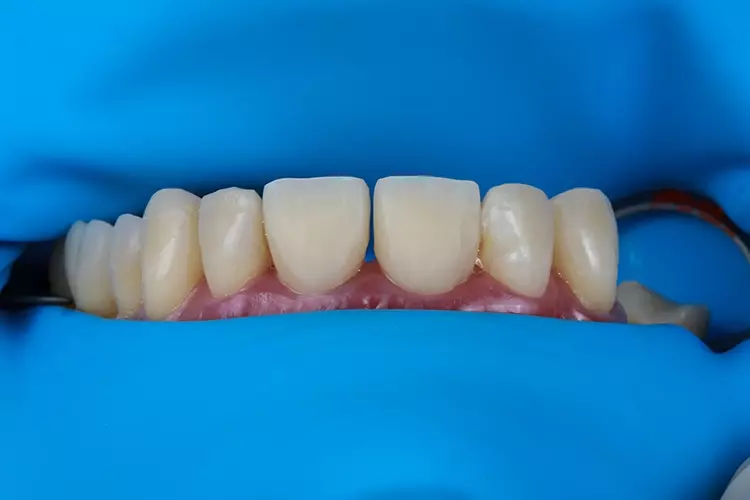

Die Kronen für 11 und 21 wurden mit einer 5-Achs-Fräs- und Schleifmaschine (inLab MC X5; Dentsply Sirona) aus einer nanokeramischen Komposit CAD/CAM-Ronde (Grandio disc, A1, VOCO) gefräst und mit Bifix Hybrid Abutment (VOCO) auf einem Abutment aus Metall (Grand Morse, Neodent Titanium Base Neodent, Straumann) im Labor zementiert. Die Kronen wurden in ihrer endgültigen Position eingegliedert (Abb. 18). Jede Krone wurde mit direkten Komposit-Veneers modifiziert.

Das Ergebnis entsprach den Erwartungen des Patienten. In der Nachbehandlungsphase wurde die Okklusion erfolgreich wiederhergestellt, wobei eine neue vertikale Dimension, eine passende Kronenform und -größe sowie funktionsorientierte Okklusionsebenen erreicht wurden.

Es konnten sofortige positive ästhetische und funktionelle Verbesserungen beobachtet werden, die auch 6 Monate nach Eingliederung noch deutlich sichtbar sind. Darüber hinaus wurden okklusale Stabilität und korrekte Zahnführungen erreicht.